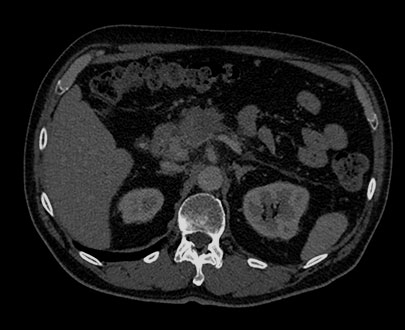

Выбирайте значение уровня энергии от 45 до 125 кВп, чтобы просмотреть структуры в соответствии с их характеристиками спектрального затухания.

В режиме MonoE показаны синтезированные моноэнергетические изображения с предустановленными значениями кВп в диапазоне от 40 до 200 кВп. При изменении значения кВп также происходят изменения на изображении, даже при сохранении настроек окна/уровня. Например, при более низком значении кВп йод может проявляться ярче, а при более высоком значении количество артефактов от металлических объектов может быть снижено.